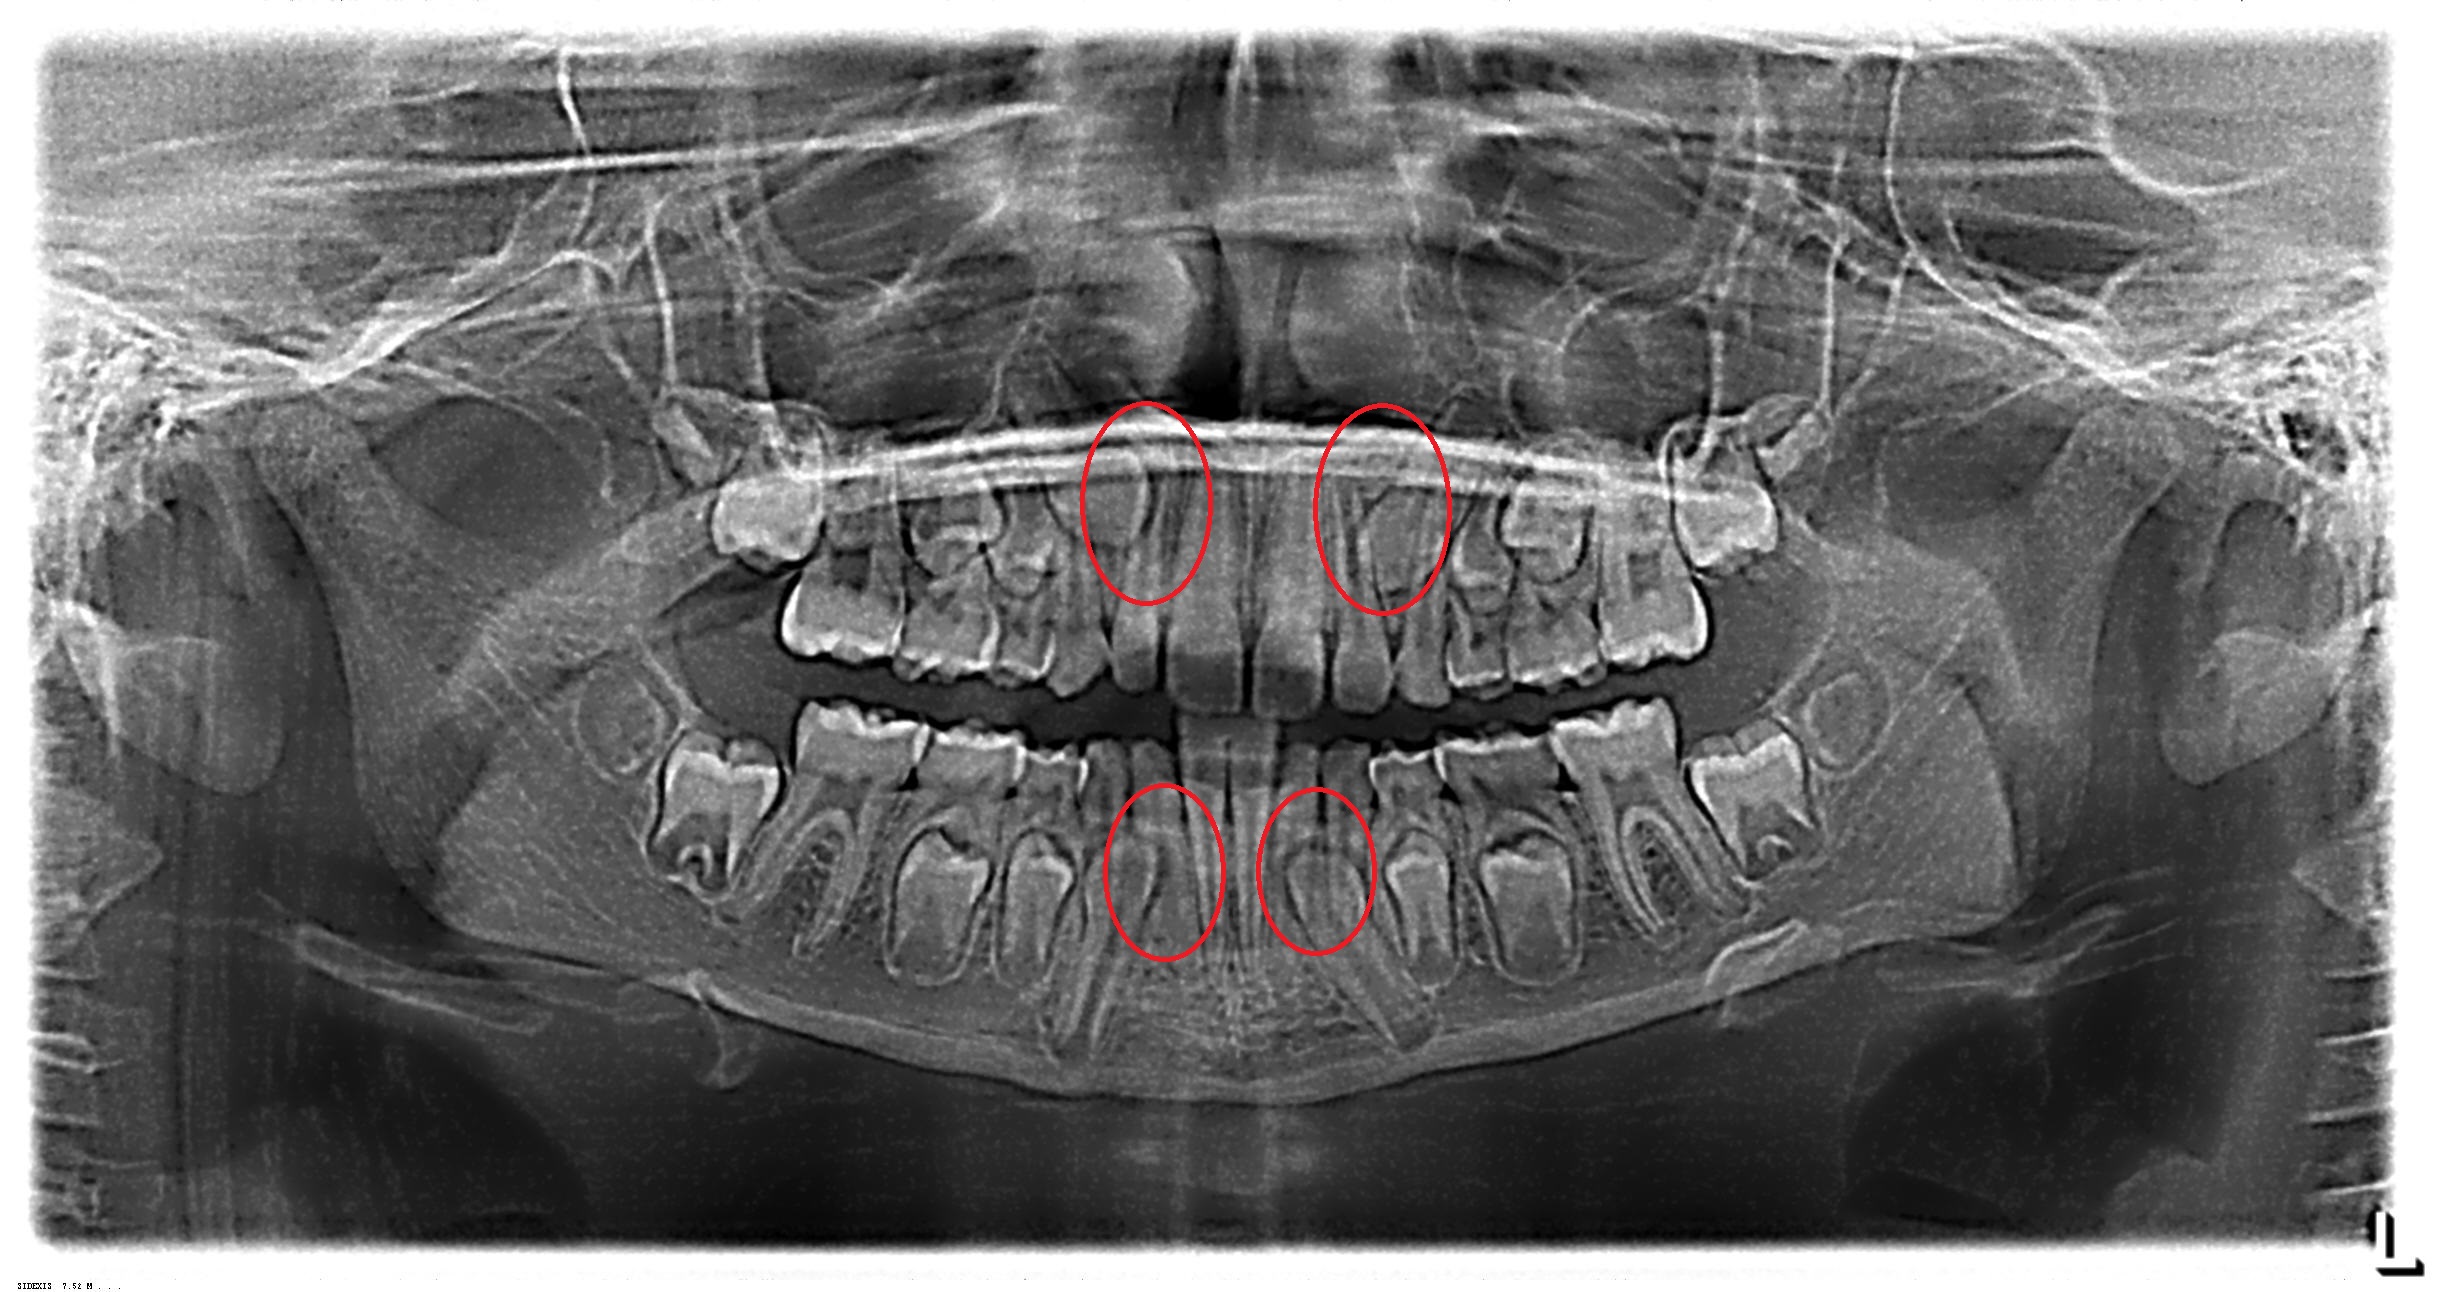

Es por eso que todos los análisis en ortodoncia deben ser diagnosticados por radiografías (en especial en edad en crecimiento 5 a 10 años, lo mas complicados desde los 3 años). Entre las radiografías que mas se utilizan estaran:

- Radiografía Panorámica

Imagenes de distintos Análisis Radiográficos.